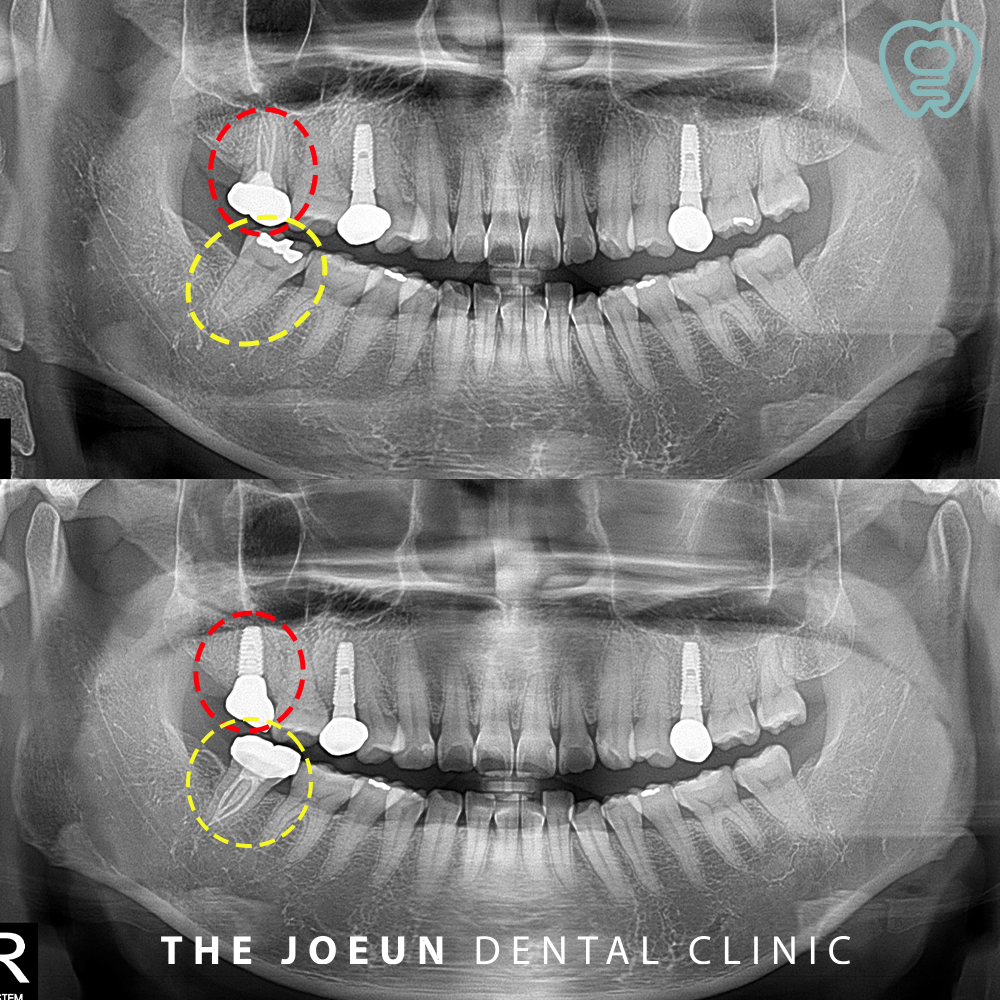

이 치아는 복잡한 C형 근관을 가진 치아였지만 안정적으로 신경치료가 마무리된 모습입니다.

한국인을 포함한 아시아계에서 하악 제2대구치에 주로 보이는 C형 근관은 정밀한 근과 형성과 충전이 어려워 신경치료의 실패율이 높은 치아입니다. 환.자의 나이가 어릴수록 많이 나타나며 여성에서 많이 나타나는 양상을 보이는데요. 이는 나이가 들수록 근관이 협착되면서 근관이 분리되는 현상이 나타나 발현율이 낮아지는 것으로 보입니다. 따라서 이러한 치아의 경우 근관치료 시 매우 주의가 필요하며, 이 단계까지 진행되지 않도록 정기적인 관리 또한 필요할 것입니다.